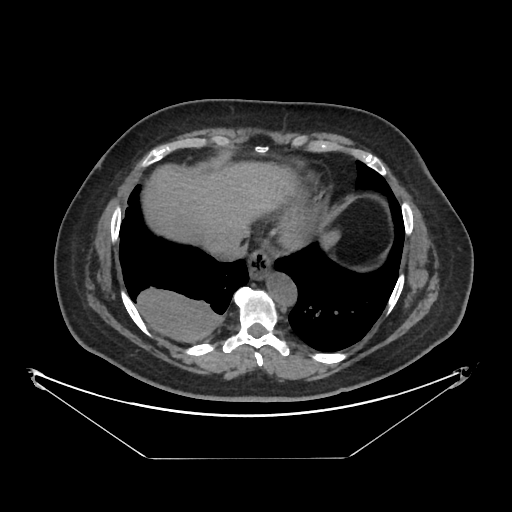

Original VENOUS CT scan

Full window (WL 1023.5, WW 4095 β†’ Low βˆ’1024, High +3071)

Lung window (WL -600, WW 1500 β†’ Low βˆ’1350, High +150)

Mediastinum window (WL 40, WW 400 β†’ Low βˆ’160, High +240)